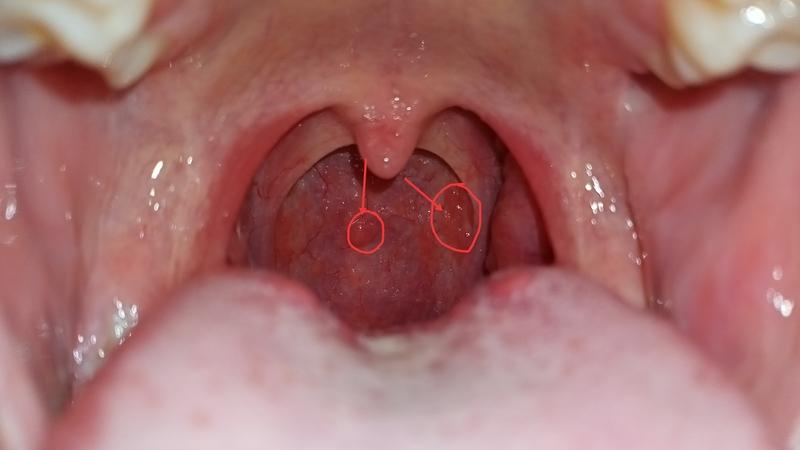

Đây là một bệnh mãn tính mà bất kỳ ai cũng có thể mắc. Do viêm nhiễm kéo dài, niêm mạc trong họng bị tổn thương, suy yếu và dễ bị virus tấn công. Từ đó tạo thành các hạt màu đỏ bên trong thành họng.